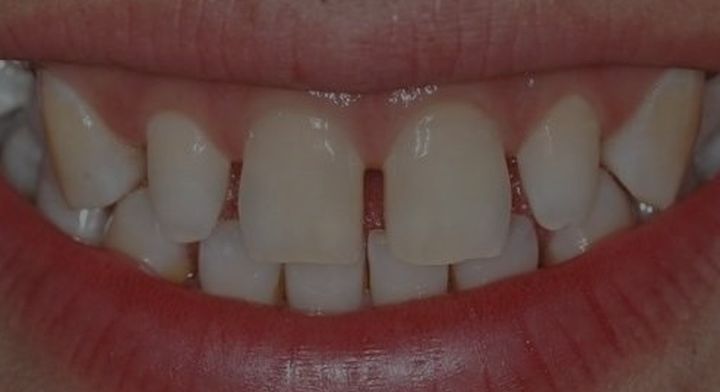

三、 既然牙齿不齐的牙齿更适合做矫正,那为什么美容冠仍然有市场

美容牙冠的存在,是因为有需求的存在,并不是所有牙齿不齐的人都有时间或者金钱去做牙齿矫正。例如很多前牙散在间隙的成年人,接受不了几万块的牙齿矫正方案,只舍得去小诊所花几千块做金属烤瓷冠关闭牙缝。

你说他们不知道牙齿矫正的方案更好?他们不知道金属烤瓷冠的弊病?大部分做全冠的人是知道的,但为什么还要退而求其次?那是因为没钱!